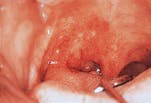

SCC on the anterior floor of mouth

The typical ton-gue lesion is seen on the the posterior lateral border, while the anterior floor of the mouth is involved more frequently than the posterior. Other locations include the soft palate, buccal mucosa, and gingiva.